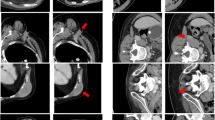

In addition, the expert scoring results were graphically interrelated with the quantitative results of DSC and 1‑(HD)/50 mm values in order to support the quantitative assessment (Fig. 4). Principally, AS structures scored with 1 show higher DSCs and lower HDs than those scored with 2 or 3. However, in five cases with relatively high HDs for the spinal cord (>25 mm), clinical acceptance was still good (40% with score 1 and 60% with score 2, no score 3). In another patient, the left and right lung were scored with 3—the cause of these unacceptable results was a postoperative loss of four vertebrae (Fig. 5 left)—even though the DSCs showed acceptable results (0.85 and 0.79, respectively). The HDs in this case were >50 mm. One more example of a not-accepted AS of the left kidney is shown in Fig. 6. The auto-segmented contour of the left kidney totally involved the big psoas muscle because of direct contact of both organs (see sagittal view).

Example of a set of auto-segmented structures scored 3 in axial, coronal, sagittal view with three-dimensional reconstruction (postoperative CT). For illustrative purposes the visualization of auto-segmented objects was modified to show surfaces/volumes instead of contours. DSC Dice similarity coefficient, HD Hausdorff distance, L left, R right, CT Computed Tomography